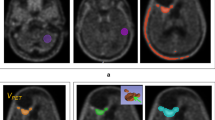

To extract time–activity curves (TACs) for each individual slice with suspicious [18F]FET uptake, 90 % isocontour threshold ROIs were defined on a summed image (10–30 min p.i.) and applied to the dynamic PET data (Fig. 1). According to the kinetic analysis, the lesions were classified into the following five groups: (1) homogeneously increasing TACs, (2) predominantly increasing TACs, (3) 50 % increasing and 50 % decreasing TACs, (4) predominantly decreasing TACs, and (5) homogeneously decreasing TACs.